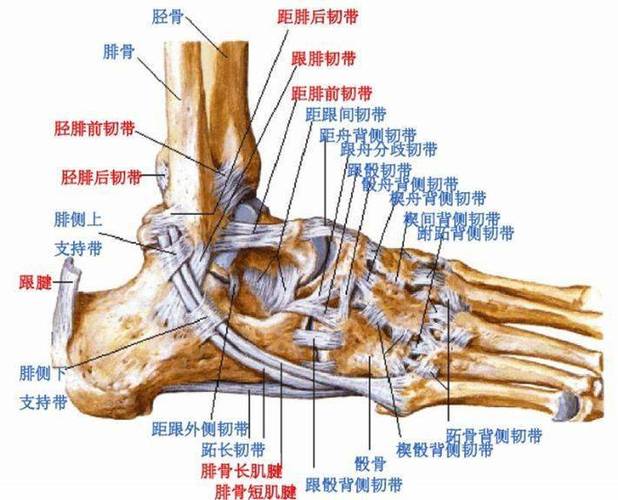

高清图解踝关节韧带解剖

踝关节解剖分析

值得收藏踝关节解剖分析高清图文详解

踝关节损伤的病因如何处理以及预防措施(附踝关节解剖

踝关节损伤的病因如何处理以及预防措施(附踝关节解剖